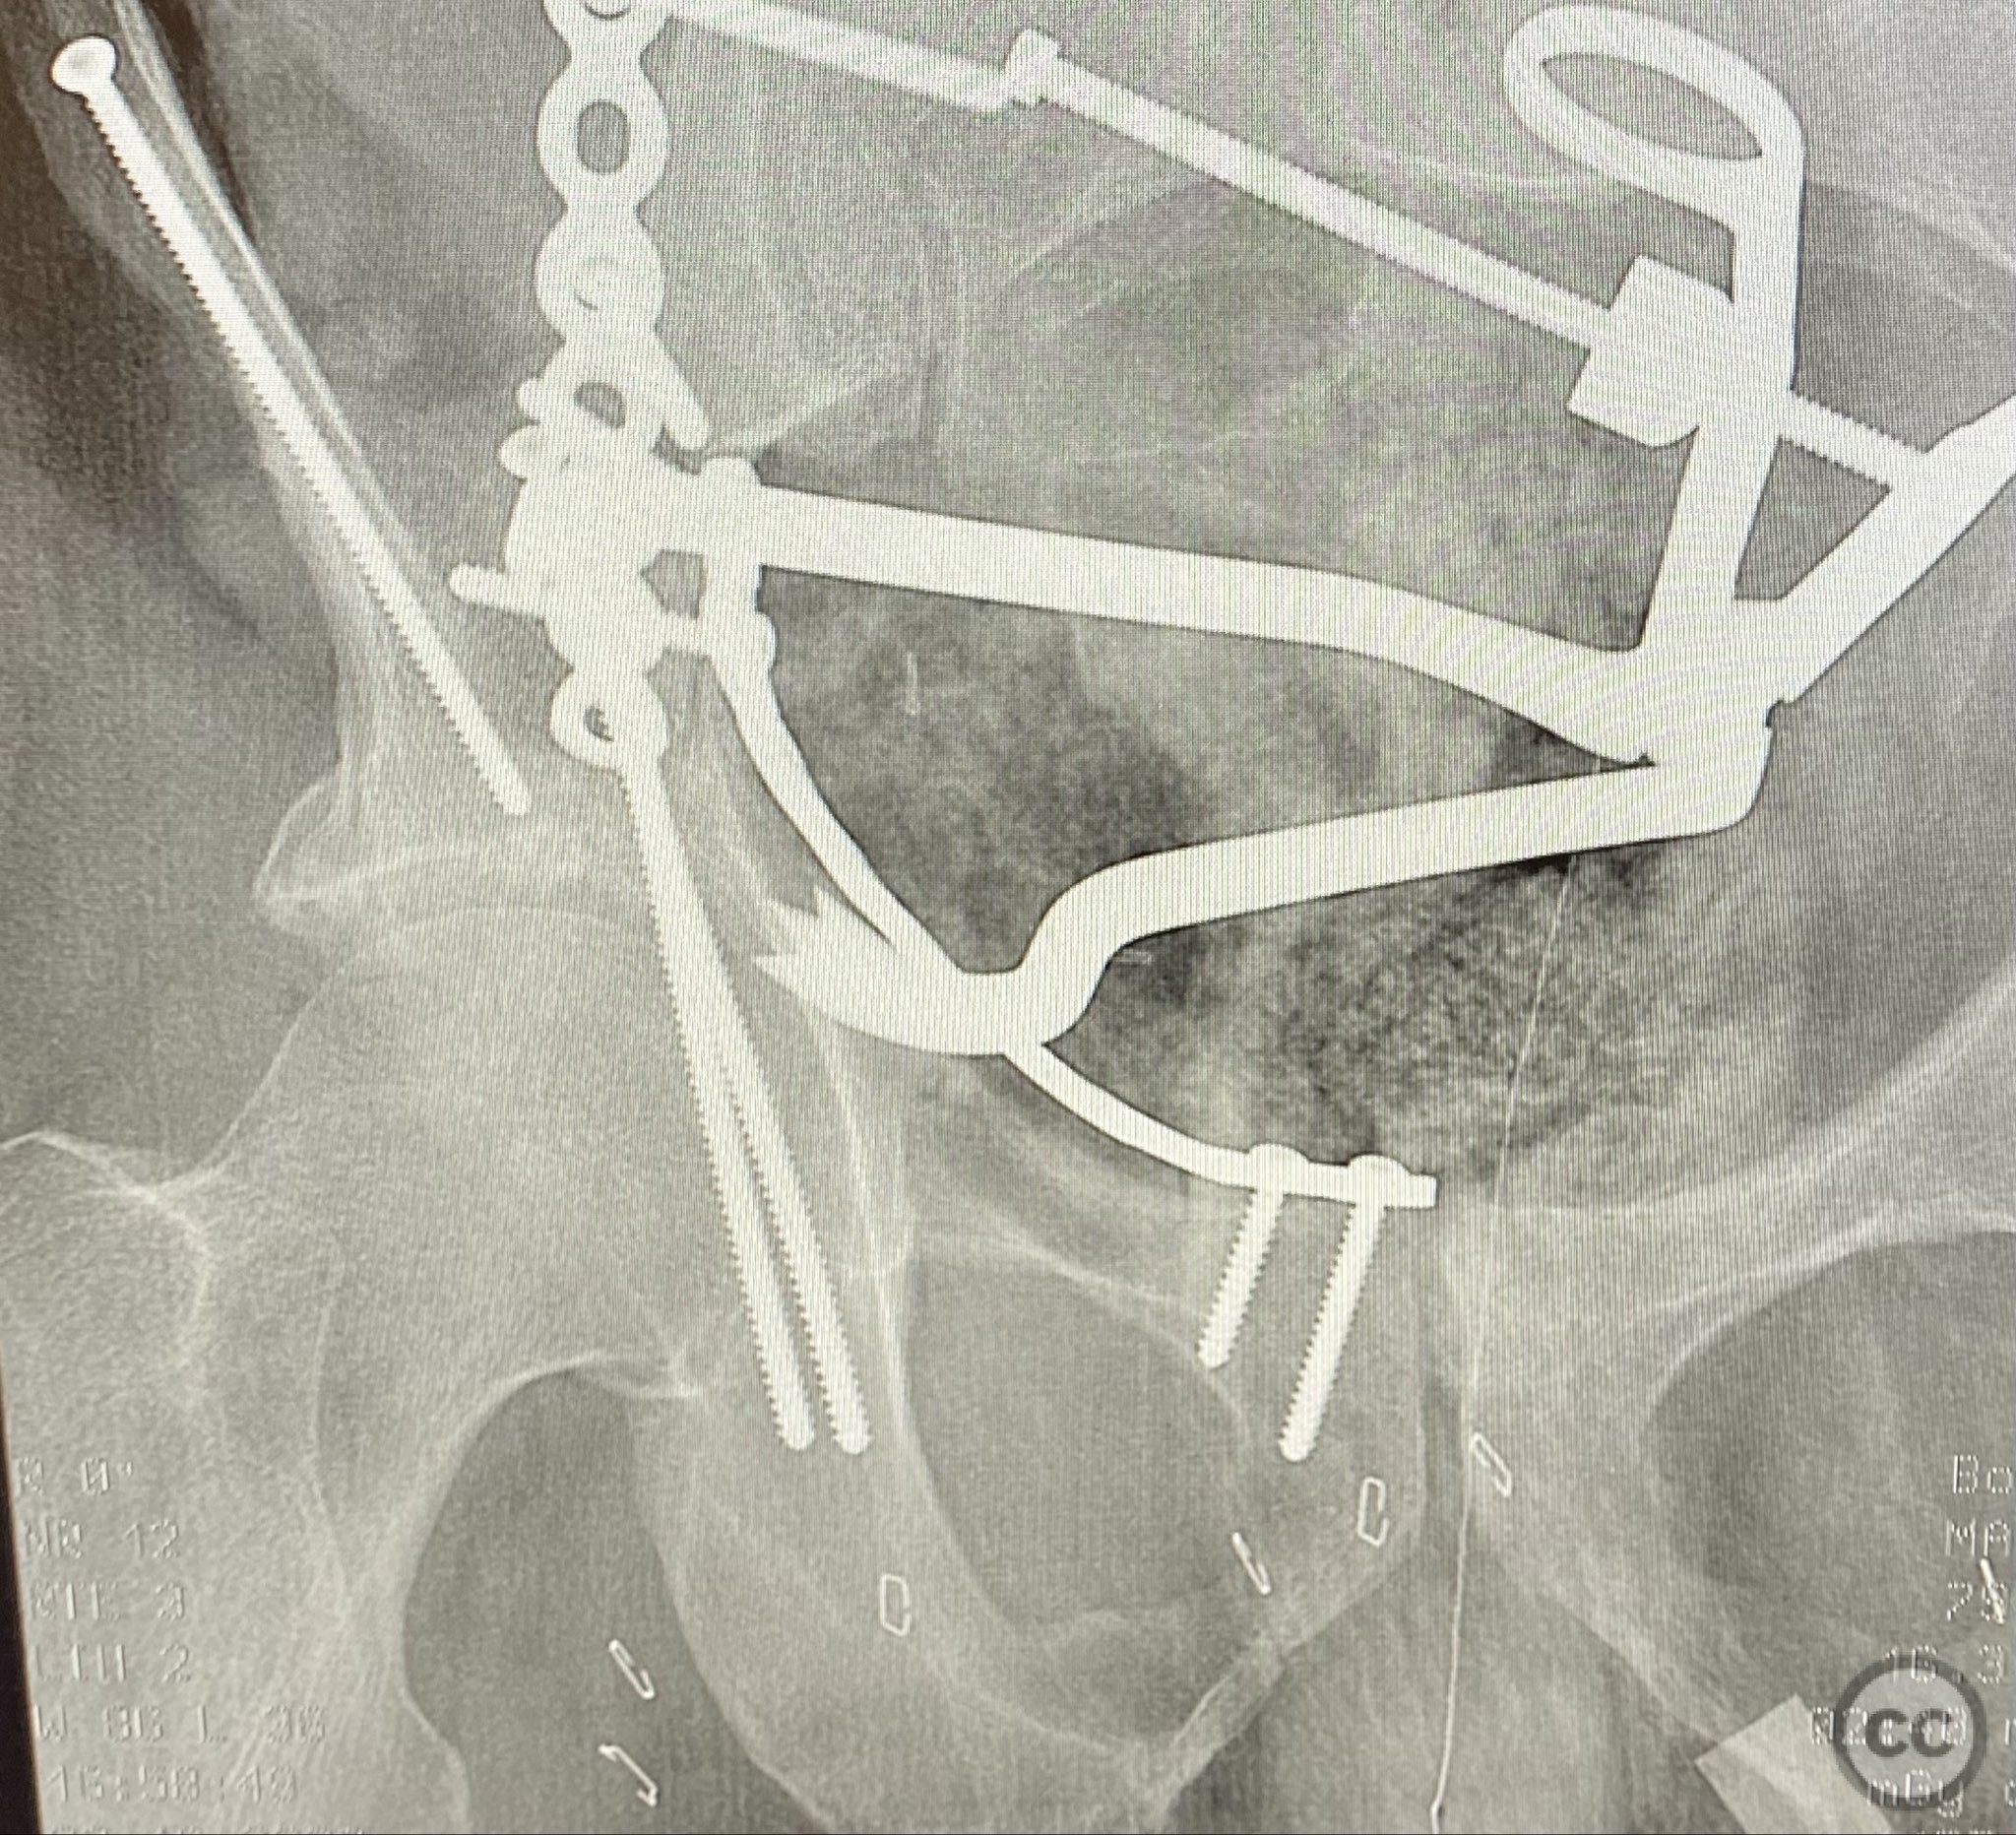

Anatomical surgical approach:  A standard ilioinguinal approach was performed, sequentially developing the iliac, middle, and intrapelvic windows. Subperiosteal dissection exposed the fractured anterior column and quadrilateral plate. The fracture planes were meticulously debrided of hematoma and interposed tissue. Bone clamps were applied to achieve reduction of the anterior column and posterior hemi-transverse fragments. Buttressing plates were contoured and applied to the pelvic brim and quadrilateral surface, with interfragmentary lag screws placed through the plates to secure the reduction while maintaining clamp control.

Operative remarks:

Surface renderings from preoperative imaging facilitated intraoperative correlation between radiographic and fluoroscopic views, aiding in precise interpretation of fragment orientation during reduction. The use of focal plates allowed for maintenance of provisional reductions with bone holding clamps during definitive fixation. Restoration of radiographic lines was confirmed on intraoperative AP fluoroscopy, while postoperative axial CT demonstrated successful central dome repair with a residual edge crush defect at the dome margin.